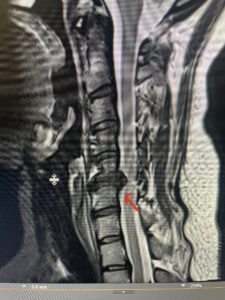

Fig 2a Sagittal and axial T2 weighted cervical MRIs demonstrating large C4 5 herniated disc with spinal cord compression red arrows

This 47-year-old male who four months prior was lifting weights developed sharp pain in his neck. After that he developed progressive numbness in his arms, neck pain and headache. He said that the right arm was worse than the left. On examination the patient had long tract weakness on the right side which included his triceps, finger extensors, hip flexors, and dorsiflexors. The patient did not have hyperreflexia. MRI (Fig. 2) demonstrated a massive, extruded disc herniation with severe cord compression. The patient because of progressive myelopathy and spinal cord compression was indicated for anterior cervical discectomy and fusion at C4-5 (Fig. 3). Patient had significant improvement of weakness and numbness post operatively.

Fig. 2a Sagittal T2-weighted cervical MRI demonstrating large C4-5 herniated disc with spinal cord compression (red arrow)

Fig: 2b Axial T2-weighted cervical MRI demonstrating spinal cord compression from C4-5 herniated disc (red arrow)